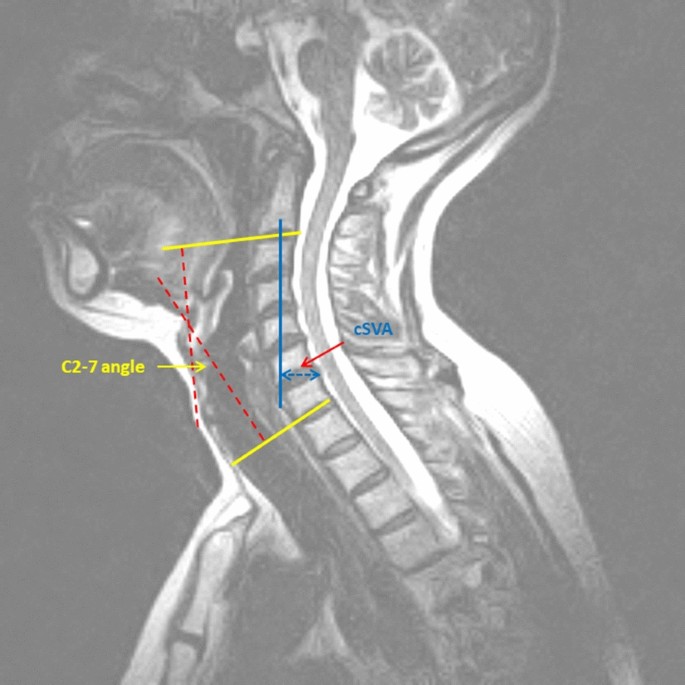

Being the most mobile segment of spine, cervical spine tends to reciprocally align itself in both sagittal and coronal planes in response to any alteration in the contour throughout the reminder of vertebral column 1. This alignment helps prevent excessive anterior. An understanding of this anatomy is essential for the spinal canal is triangular, with the apex posterior and rounded edges.

The human spinal column is composed of seven cervical vertebrae, 12 thoracic vertebrae, five lumbar vertebrae, five sacral in the sagittal plane, however, a physiologic amount of curvature can be seen within the different spinal regions: This mri cervical spine sagittal cross sectional anatomy tool is absolutely free to use. Learn about the regions of spine and their complex functions in daily life. This guide gives a general overview of the anatomy of the thoracic spine.